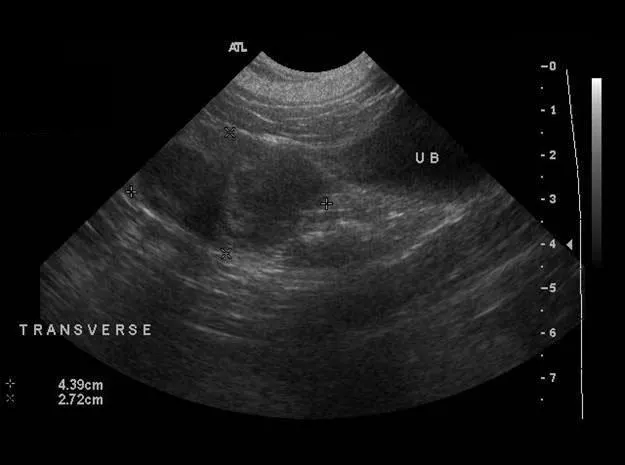

On abdominal ultrasonography, a 15 × 18–mm cystic mass was noted caudolateral to the right kidney (Figure 1C). A second mass (Figure 1D) located dorsal to the urinary bladder and measuring 4.39 × 2.72 cm high (sagittal view) was filled with flocculent fluid. Escherichia coli organisms were isolated on aerobic culture of the vagina.

The perinephric mass and the uterine stump were removed via laparotomy (Figures 1E, 1F, and 1G). Histopathology identified a luteoma originating from a right ovarian remnant as well as uterine stump pyometra with endometrial progesterone influence.